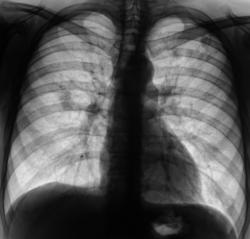

При расшифровке цифровых флюорограмм пациент "взят на контроль". Проведено стандартное дообследование, после которого пациент - направлен к фтизиатрам. Фтизиатры с большим удовольствием занялись пациентом.

Выставили фтизиатры "инфильтративный туберкулёз".